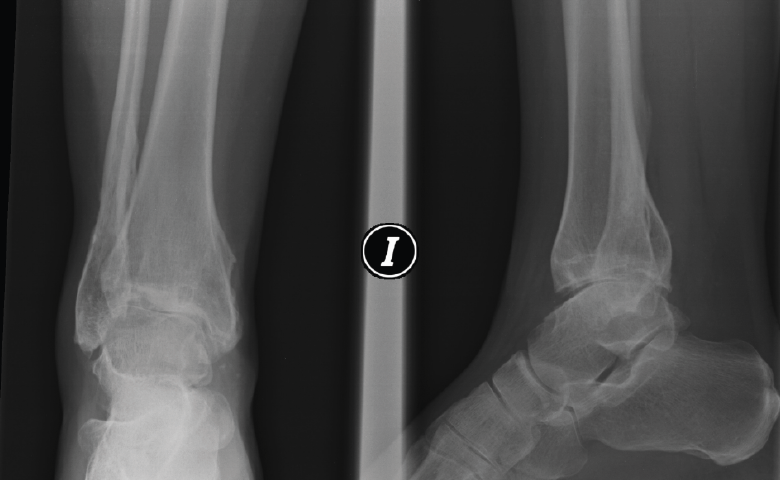

Figura 4. A y B: radiografías anteroposterior y lateral del fijador implantado con la distracción conseguida a nivel articular.